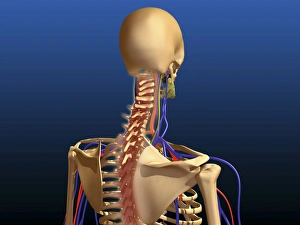

The scapula, also known as the shoulder blade, is a crucial bone in our body that plays a significant role in our mobility and stability. It forms part of the pectoral girdle and connects the upper arm to the thorax. When we examine diagrams of the bones of the hand and arm, we can see how intricately connected they are to the scapula. This connection allows us to perform various movements with precision and control. In an anterior view total shoulder joint repair image, we witness medical advancements aimed at restoring functionality to this vital joint. The intricate procedure highlights just how important it is to maintain a healthy scapula for optimal movement. Shoulder muscles artwork showcases their attachment points on the scapula, emphasizing their role in providing strength and stability during physical activities. Understanding these muscles helps us appreciate their contribution to everyday tasks like lifting or throwing. A front view of female anatomy highlighting the endocrine system reminds us that even though not directly related to the scapula, every part of our body works together harmoniously. Hormones secreted by glands within this system influence bone health and development. An anterior view of human skeletal system with labels gives us a comprehensive understanding of where exactly our scapula fits into this complex framework. It serves as an anchor point for numerous ligaments and tendons essential for proper functioning. Pictograms on an ox scapula depict ancient rituals performed to ward off danger—a testament to how cultures throughout history recognized its significance beyond mere anatomy. These artifacts remind us that humans have long understood its importance in daily life. The skeleton of an eagle after Milne-Edwards engraving demonstrates nature's adaptation at its finest—the bird's wingspan relies heavily on strong shoulder blades (scapulas) allowing it effortless flight through vast skies. Haydon's Curtius engraving captures another artistic representation showcasing human form—this time focusing on muscular structure including the scapula.